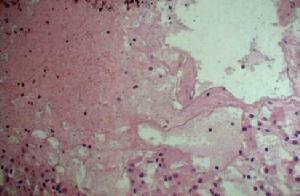

病理圖發熱一般持續1~3天,可有腹膜炎表現,且便秘多於腹瀉,胸膜炎常見,如果不及時診斷,家族性地中海熱的腹膜炎常常導致不必要的急腹症外科手術。發病通常在幾天內自發緩解。關節痛是家族性地中海熱的常見症狀,關節炎通常累及單個大關節伴隨急性疼痛和腫脹,通常2~3天后消退,雖然也有持續時間長的,尤其如果累及髖關節,腫脹是輕微的,但疼痛可以很嚴重。較其他大多數周期性關節炎綜合徵,永久性關節損害不發生。心包炎少見。3%青春期男孩有陰囊痛,皮膚表現偶見,主要為丹毒樣紅斑,直徑10~25cm,多在腰部以下部位,以及分散的壓痛性紫斑。10%~50%有脾大,AA型(蛋白源性澱粉樣物質)澱粉樣變多見,約20%,以猶太人中發生率最高達2%,可出現蛋白尿、腎病綜合徵等。

包括血沉、滑液白細胞計數在發作期升高,有核左移,IgG、IgM中度增加,10%IgD、25%IgA增加,RF、ANA陰性。澱粉樣變的確診依據主要是組織切片經剛果紅染色後在偏光顯微鏡下呈特徵性蘋果綠雙摺光,如AA蛋白單克隆抗體染色陽性,則對AA型澱粉樣變的診斷有重要價值。

c)直腸活檢或腎臟活檢:直腸活檢是從直腸部位取下一小塊組織,直腸活檢非常容易做。如果直腸活檢未見到澱粉樣變,那么就需要做腎臟活檢來確診。做腎臟活檢時,患兒需在醫院住一夜。活檢組織染色後在顯微鏡下檢查有無澱粉樣物沉積。

3.直腸活檢或腎臟活檢:直腸活檢是從直腸部位取下一小塊組織,直腸活檢非常容易做。如果直腸活檢未見到澱粉樣變,那么就需要做腎臟活檢來確診。做腎臟活檢時,患兒需在醫院住一夜。活檢組織染色後在顯微鏡下檢查有無澱粉樣物沉積。